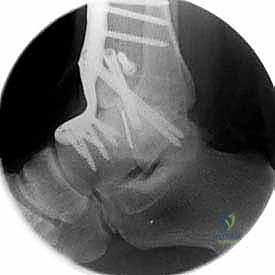

| طرق العلاج | أدوية مضادة للالتهابات (NSAIDs)، أحذية طبية مخصصة (Rocker-bottom shoes)، دعامات الكاحل (AFO)، حقن الكورتيزون أو البلازما (PRP)، العلاج الطبيعي. | جراحة إزالة الغضاريف التالفة ودمج العظام (Arthrodesis) باستخدام مسامير وألواح معدنية. |

- رؤية ممتازة للمفصل: يوفر المدخل الأمامي رؤية بانورامية واسعة ومباشرة لكامل السطح المفصلي للظنبوب وعظم الكاحل، مما يسمح بإزالة الغضاريف التالفة بدقة متناهية.

- تصحيح التشوهات بدقة: يسمح هذا المدخل بتعديل انحرافات الكاحل (سواء كان يميل للداخل Varus أو للخارج Valgus) وإعادته إلى المحور الميكانيكي الطبيعي للساق.

- تثبيت ميكانيكي حيوي أقوى: يتيح المدخل الأمامي وضع شريحة معدنية (Anterior Plate) على الجانب الأمامي للمفصل. من الناحية الميكانيكية الحيوية (Biomechanics)، يعتبر الجانب الأمامي هو "جانب الشد" (Tension side) أثناء المشي. وضع الشريحة هنا يوفر تثبيتاً فائق القوة ويقلل من معدلات عدم الالتئام.

- التخطيط الجراحي الرقمي: باستخدام صور الأشعة المقطعية، يقوم الدكتور هطيف بتخطيط الجراحة على الكمبيوتر لاختيار حجم المسامير والشرائح المناسبة بدقة مليمترية.

خطوات جراحة تثبيت مفصل الكاحل الأمامي بالتفصيل (Step-by-Step Surgical Procedure)

تُجرى العملية تحت التخدير العام أو النصفي (الشوكي)، وتستغرق عادةً بين ساعتين إلى ثلاث ساعات، وتتطلب دقة ومهارة فائقتين. إليكم الخطوات الجراحية كما ينفذها الأستاذ الدكتور محمد هطيف: